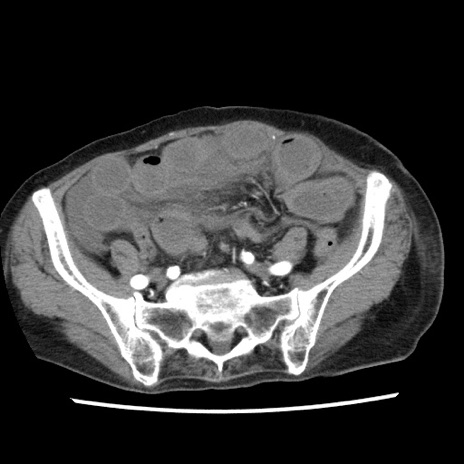

症例1(横断像)

【症例】80歳代女性

【主訴】腹痛

【現病歴】8時間前から腹痛あり来院。

【既往歴】糖尿病、脂質異常症、子宮体癌にて子宮全摘術

【身体所見】意識清明・会話良好だが腹痛で苦悶様、全腹部にわたって反跳痛と圧痛あり

【データ】WBC 13600、CRP 0.14、LDH 224、CK 90